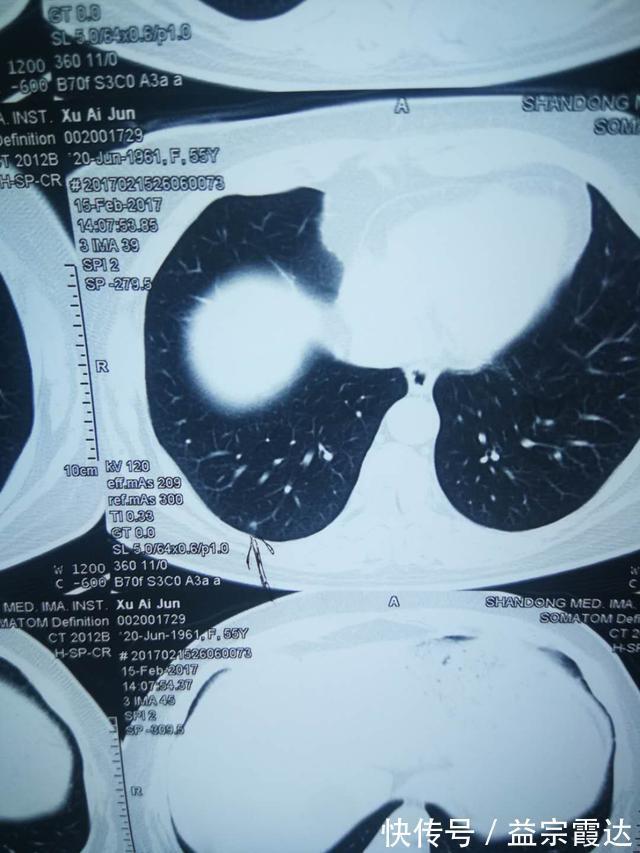

>许女士的CT报告北京中医药大学东方医院 肿瘤科主任 / 副教授 / 硕士生导师国家肿瘤微创联盟中西医结合肿瘤微创专委会候任主委BTV《养生堂》、山东卫视《大医本草堂》特约专家